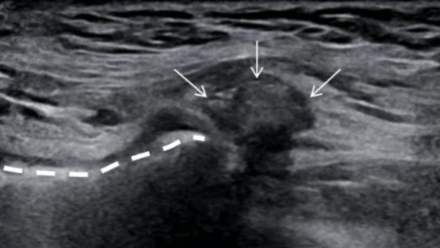

Test du valsalva

Hernie fémorale